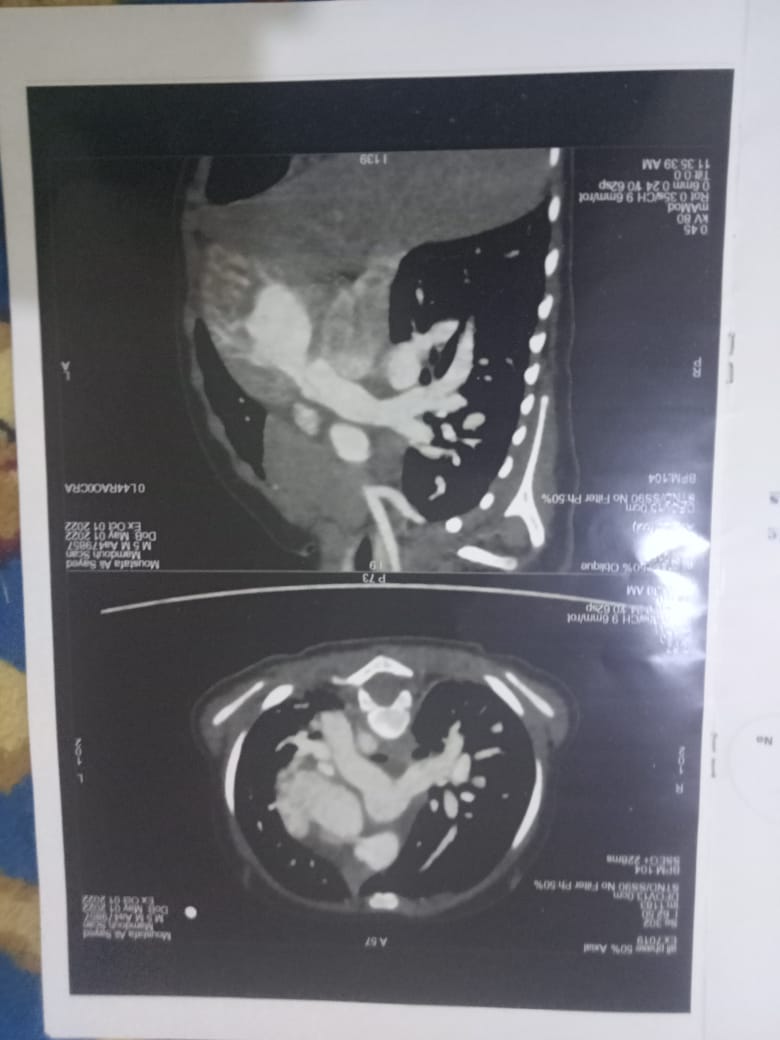

وأكد والد الطفل أن لديهم الأوراق وصور الأشعة والتحاليل والتقارير، التي يؤكد من خلالها الأطباء على إصابة الطفل مصطفى بثقب في القلب مع ضرورة العلاج.